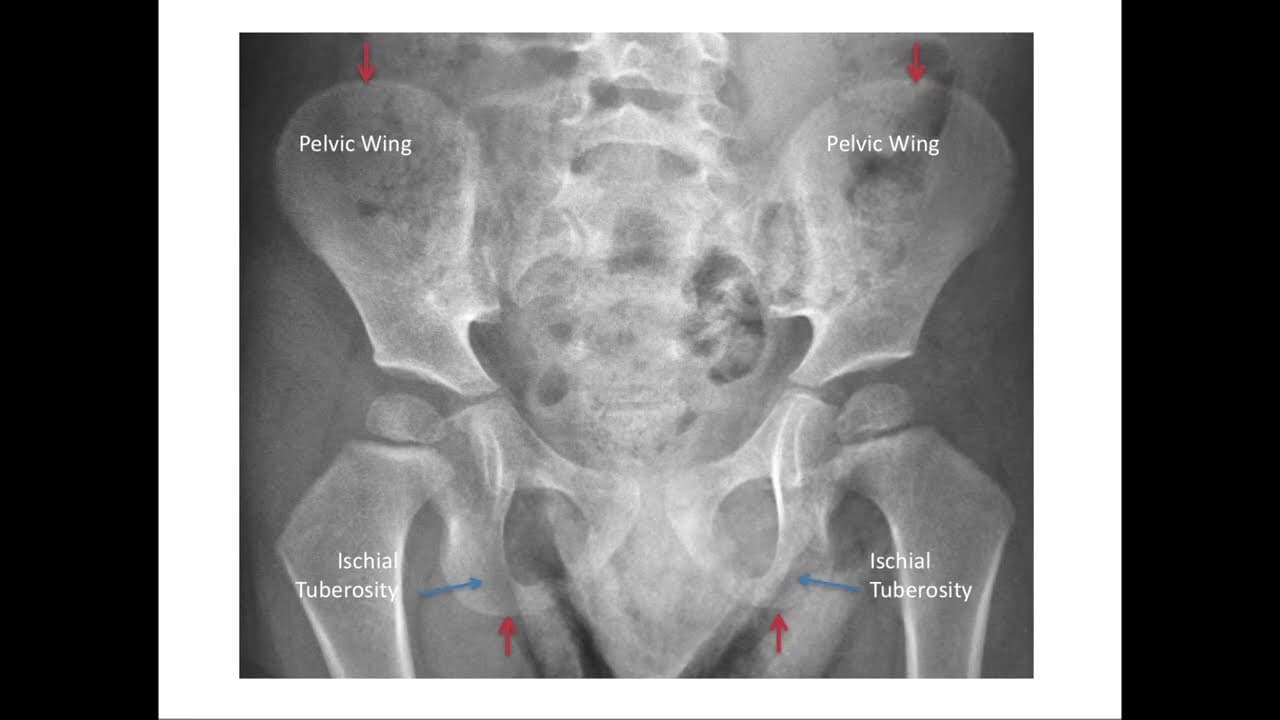

The tri-radiate cartilage is the growth center of the hip socket and appears as a thick line outlined here with arrows. The red arrow shows the outermost margin of the tri-radiate cartilage, another important landmark for measuring migration percentage. The pelvis has two other important landmarks, the pelvic wings and the ischial tuberosities, which are both labeled here. The red arrows mark the uppermost margin of the pelvic wings and the lowermost margin of the ischial tuberosities, and both of these can be used as landmarks for measurement of the migration percentage.